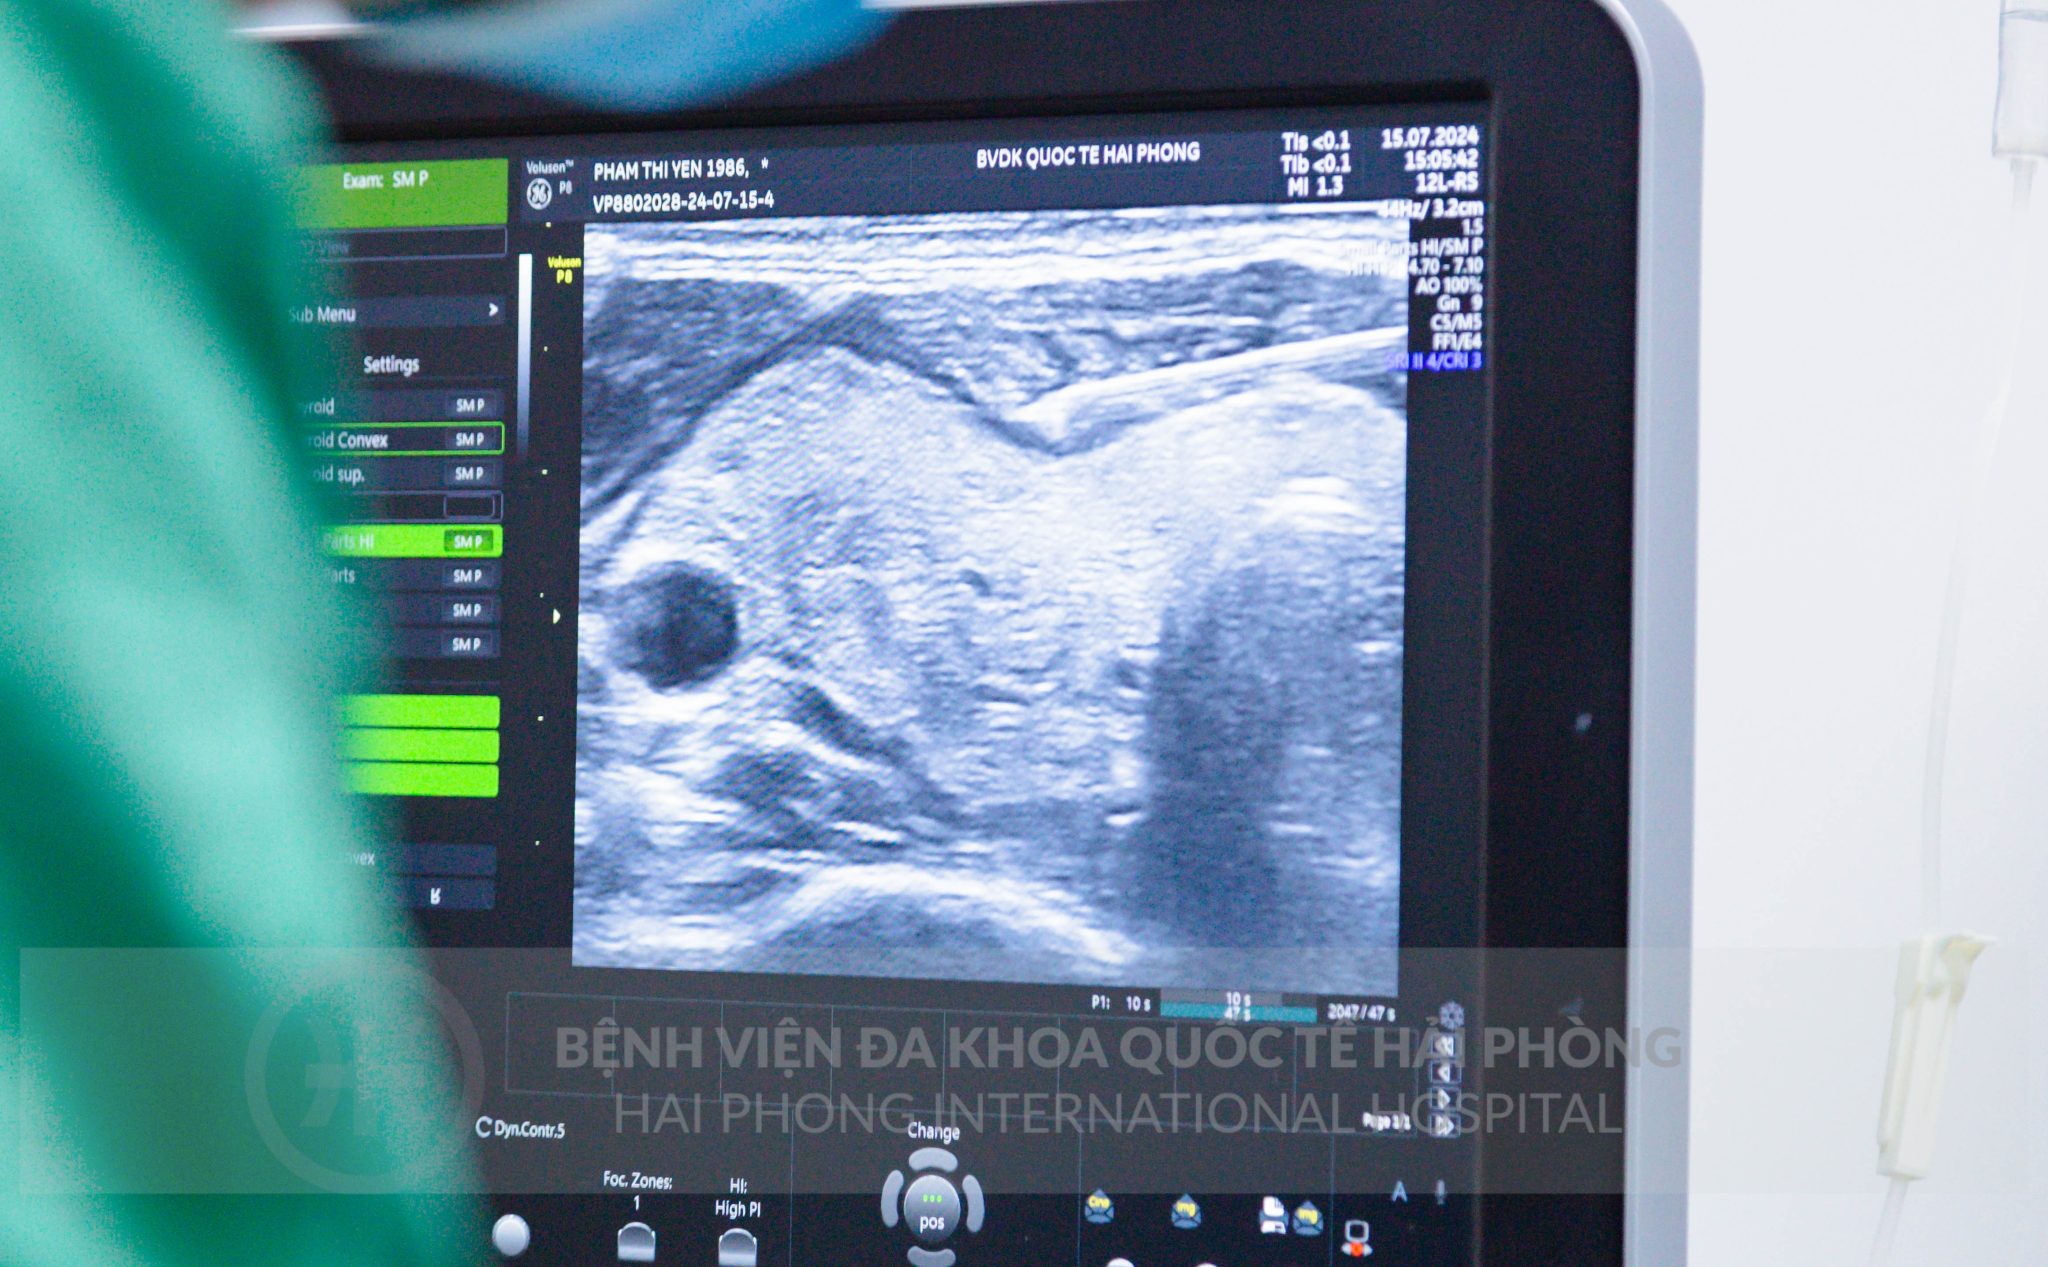

– KHÔNG MỔ: Sử dụng sóng cao tần “tiêu diệt” khối u dưới hướng dẫn của siêu âm.

– Hệ thống trang thiết bị hiện đại như: Máy đốt sóng cao tần (RFA), Siêu âm màu, siêu âm đàn hồi mô tuyến giáp…